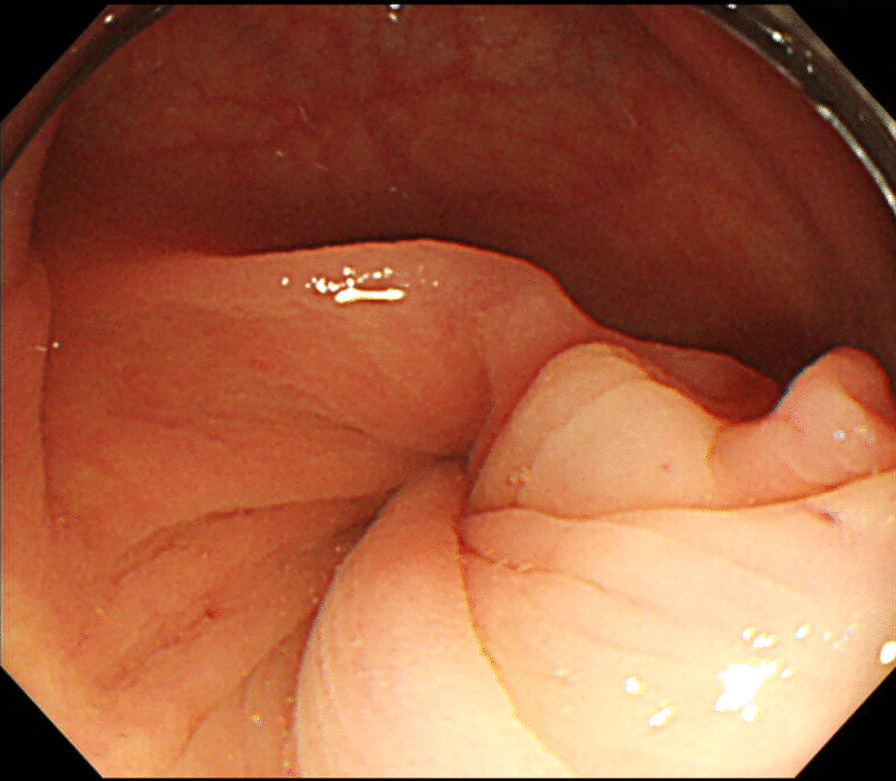

A 53-year-old female with a history of rheumatoid arthritis and thyroid tumor was referred to our hospital. The patient’s chief complaint was abdominal pain for 1 day, and she had no history of abdominal surgery or trauma. Upon admission, she had right abdominal tenderness. Blood tests showed unremarkable results (white blood cell count, 4800/μL; red blood cell count, 4.78 × 106/μL; hemoglobin, 14.8 g/dL; hematocrit, 43.7%; platelets, 20.7 × 104/μL; C-reactive protein, 0.59 mg/dL; creatine kinase, 50 U/L; carcinoembryonic antigen, 2.0 ng/mL; and carbohydrate antigen 19–9, 12 U/mL). Contrast-enhanced computed tomography (CT) revealed intestinal torsion at the hepatic flexure (Fig. 1). A colonoscopy was performed to evaluate the cause of the intestinal torsion, which revealed twisted mucosal folds in the transverse colon but no obvious neoplastic change on the mucosal surface (Fig. 2). The scope could not be advanced past the torsion of the transverse colon, making it impossible to observe the superior colon.

Fig. 2.

Colonoscopy showing twisted mucosal folds in the transverse colon. No obvious neoplastic change was noted on the mucosal surface